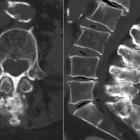

This process can result in degenerative hypertrophy, inflammatory change (as seen in case 1) and even a pseudoarthrosis with bursa formation. This interspinous bursa may extend between the ligamenta flava in the midline forming an epidural cyst and further contributing to the already existing canal stenosis .

Plain radiograph and CT

- often shows close approximation and contact of adjacent spinous processes (kissing spines)

- resultant enlargement, flattening, and reactive sclerosis of apposing interspinous surfaces

MRI

May demonstrate interspinous bursal fluid and posterocentral epidural cyst(s). MRI can be very helpful in determining whether there is resulting posterior compression of the thecal sac.